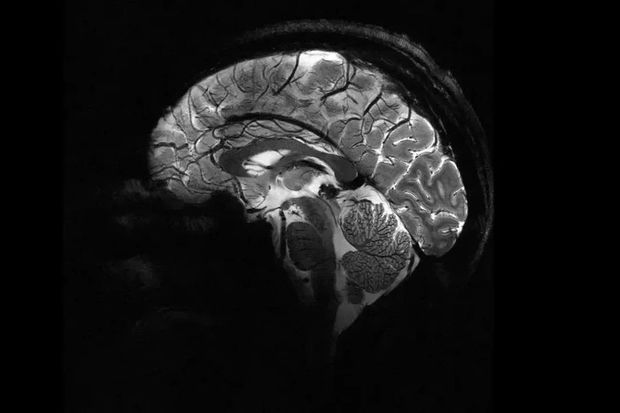

Elm adamları insan beyninin ən aydın görüntüsünü dərc ediblər. Şəkli dünyanın ən güclü maqnit rezonans tomoqrafiya (MRT) cihazı ilə əldə etmək mümkün olub.

Bildirilib ki, “Iseult” adlı MRT cihazı ilə çəkilən şəkil 20 ildən çox davam edən araşdırma nəticəsində əldə olunub.

Araşdırmalar çərçivəsində MRT cihazının son bir neçə ayda təxminən 20 sağlam könüllü üzərində sınaqdan keçirildiyi və ən aydın beyin görüntüsünün təxminən dörd dəqiqə ərzində əldə edildiyi ifadə edilib.

Açıqlamada qeyd olunub ki, 11,7 Tesla maqnit gücünə malik “Iseult” cihazı ilə qısa müddətdə çəkilən görüntüləri xəstəxanalarda istifadə edilən cihazlarla əldə etmək saatlar çəkə bilər.

“Iseult” ilə əldə edilən ultra detallı anatomik məlumatların Altsheymer və Parkinson kimi xəstəliklərin diaqnozuna kömək edəcəyi gözlənilir.